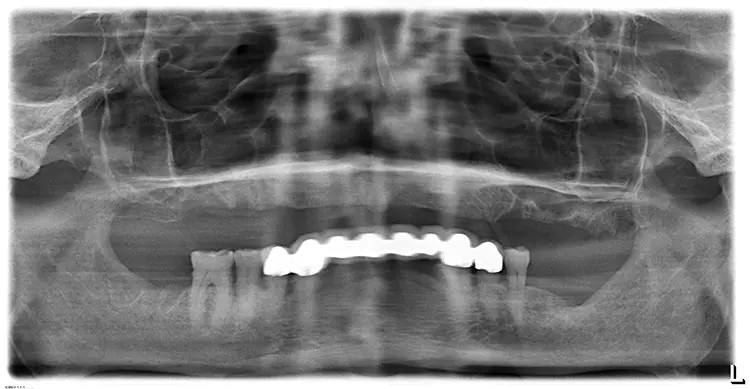

Der Patient wurde am gleichen Tag mit dem festsitzenden Brückenprovisorium entlassen und ausführlich über die Mundhygiene des Langzeitprovisoriums postoperativ aufgeklärt. Abbildung 8 zeigt eine regelrechte Implantatposition in der postoperativen Panoramaschichtaufnahme. In Abbildung 9 ist die postoperative Versorgung in situ zu sehen.